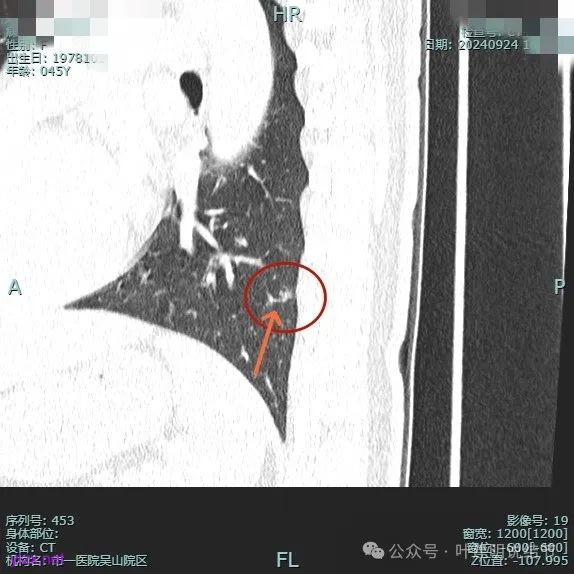

病灶1:

病灶是混合密度,边缘少许淡磨玻璃,灶内不太致密,表面不平,血管征有,但说不上明显异常增粗。

病灶紧贴叶间裂,而且感觉跨过肺叶,部分影响到上叶了,病灶本身密度虽实性为主,但是不太致密,有点松散的感觉。

总体实性部分密度较高,而磨玻璃部分密度较低,且瘤肺边界欠清,关键是跨叶间裂生长,这与肿瘤似乎不容易解释些。

毛刺有但不太锐利,磨玻璃有但偏淡,实性为但不太致密,叶间裂与之关系密切,病灶跨叶生长。

上图显得与肿瘤较为符合,但跨叶生长的话,侵袭力应该较强,可她这病灶较刚发现时进展并不太明显。

上图层面也较符合恶性,血管进入明显,有浅分叶的样子,整体觉得有一定收缩力与膨胀感。

病灶表面不平,混合密度,磨玻璃成分较淡。